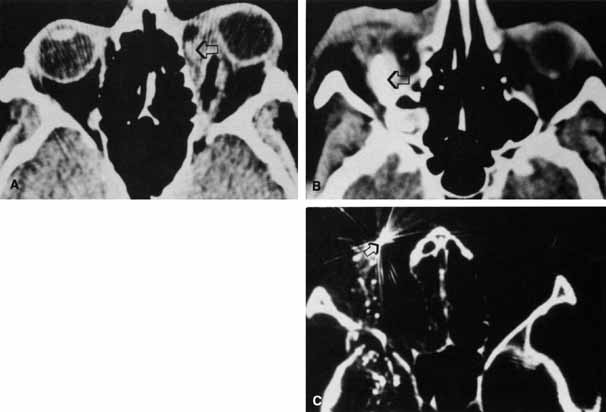

Fig. 12 In this patient (A) with right medial wall and tripod fracture, the mass effect of orbital air (B) (arrow) causes exophthalmos and contributes to hypophthalmos.